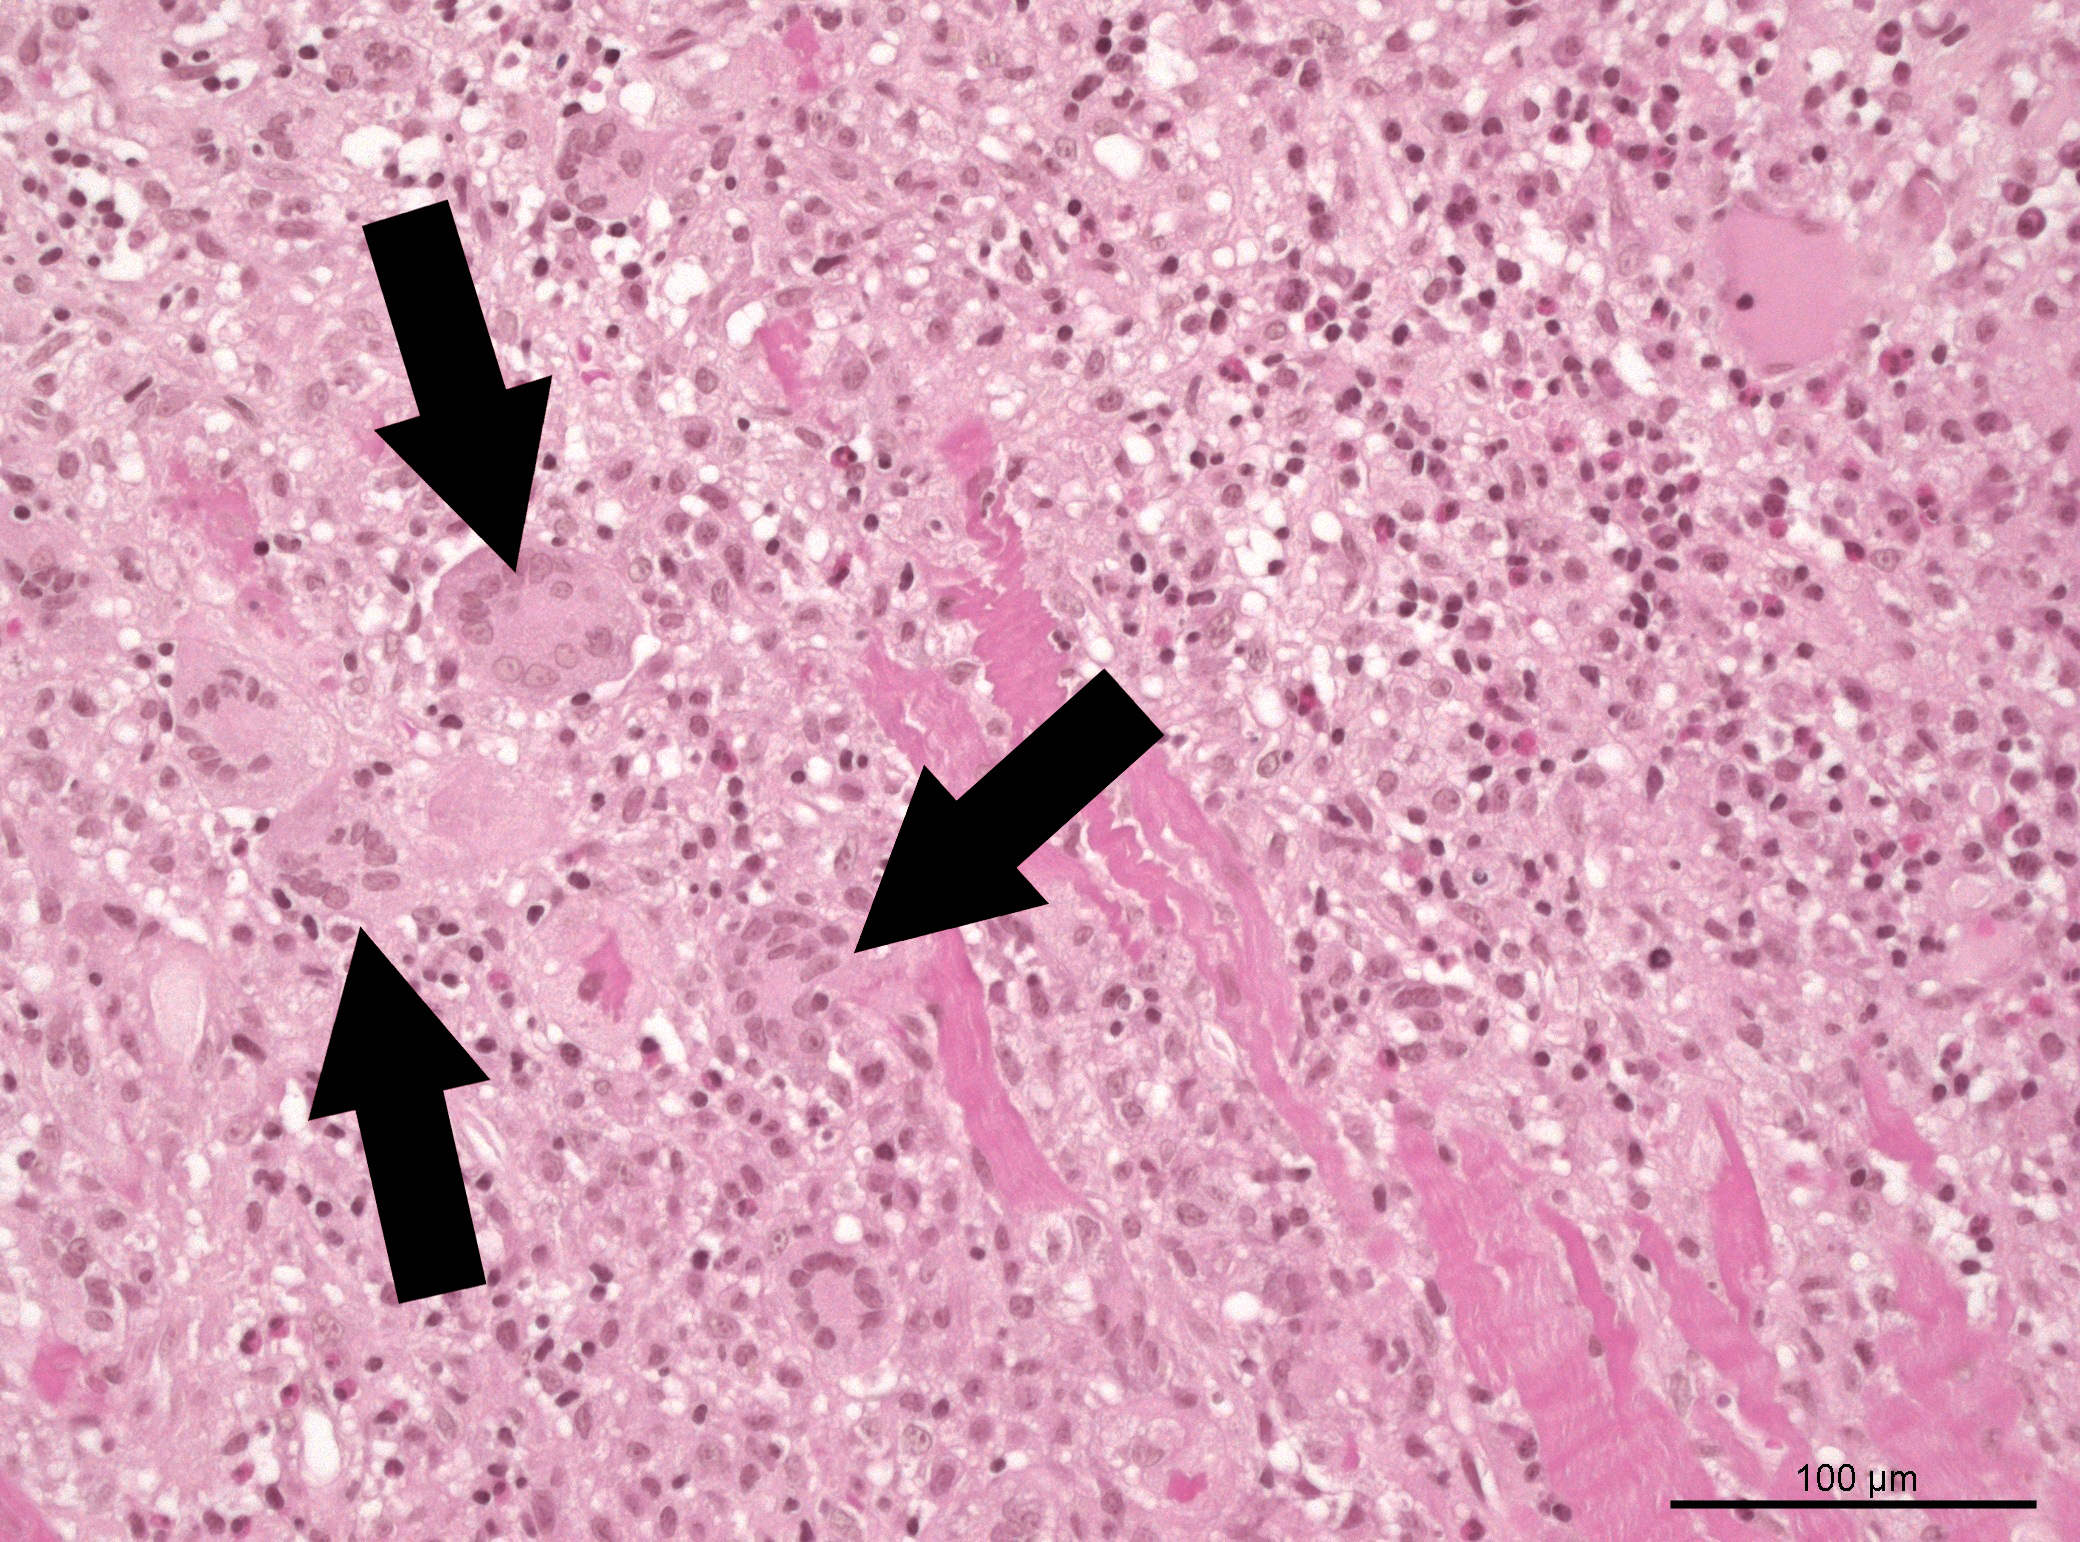

Eine erste wichtige Erkenntnis der Studie ist, dass Betroffene mit einer sogenannten Riesenzellmyokarditis – eine Sonderform, die ihren Namen aufgrund sehr großer Zellen in den Gewebeproben trägt – eine deutlich höhere Sterblichkeit aufweisen (50 Prozent), als andere Untergruppen (circa 30 Prozent). Diese Daten weisen auf die große Bedeutung der frühen Gewebeentnahme zur Probengewinnung als einen zentralen Aspekt der Diagnostik der fulminanten Myokarditis hin.

„Gerade die frühe Endomyokardbiopsie sollte bei klinisch vermuteter fulminanter Myokarditis angestrebt werden, da die histopathologischen Befunde eine entscheidende Rolle für das Management und die Prognose spielen“, ergänzt Prof. Dr. Georg Nickenig, Kardiologe und Direktor des Herzzentrums des UKB. „Denn so können wir therapeutische Konzepte und damit auch Behandlungsergebnisse bei allen Personen mit fulminanter Myokarditis perspektivisch verbessern.“